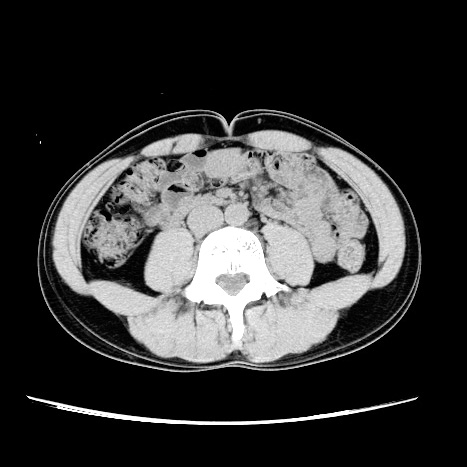

ではその「3cm」をCTで確認しましょうw。

おへそのあたりの部分です。

左が6月、右が今回の12月です。

わかりにくいので合成してみました。

おおお!!!

外側の線が6月、内側の線が12月。

背中側の脂肪が多めに減ったのか!!